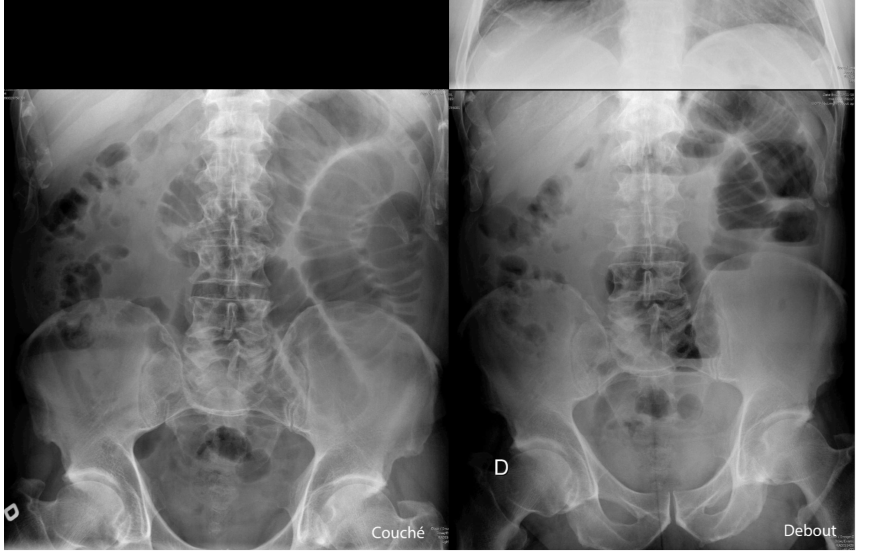

patho?

Illéus paralytique